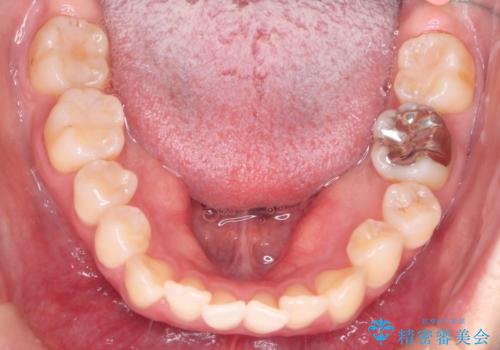

- 前歯のガタガタを主訴に来院された患者様です。

前歯の傾きも少し内側に入るように計画をたて、インビザラインにて治療を行いました。

このぐらいのガタガタであれば、インビザラインで簡単に治すことができます。